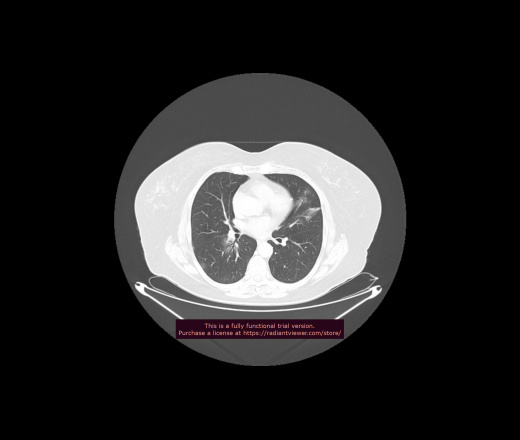

Уважаемые коллеги, если имеется интерес, сможете ли Вы спрогнозировать дальнейшее +-одинаковое течение процесса у 4 данных разных пациентов? Зацепиться где-то можно очень просто, где-то нельзя.